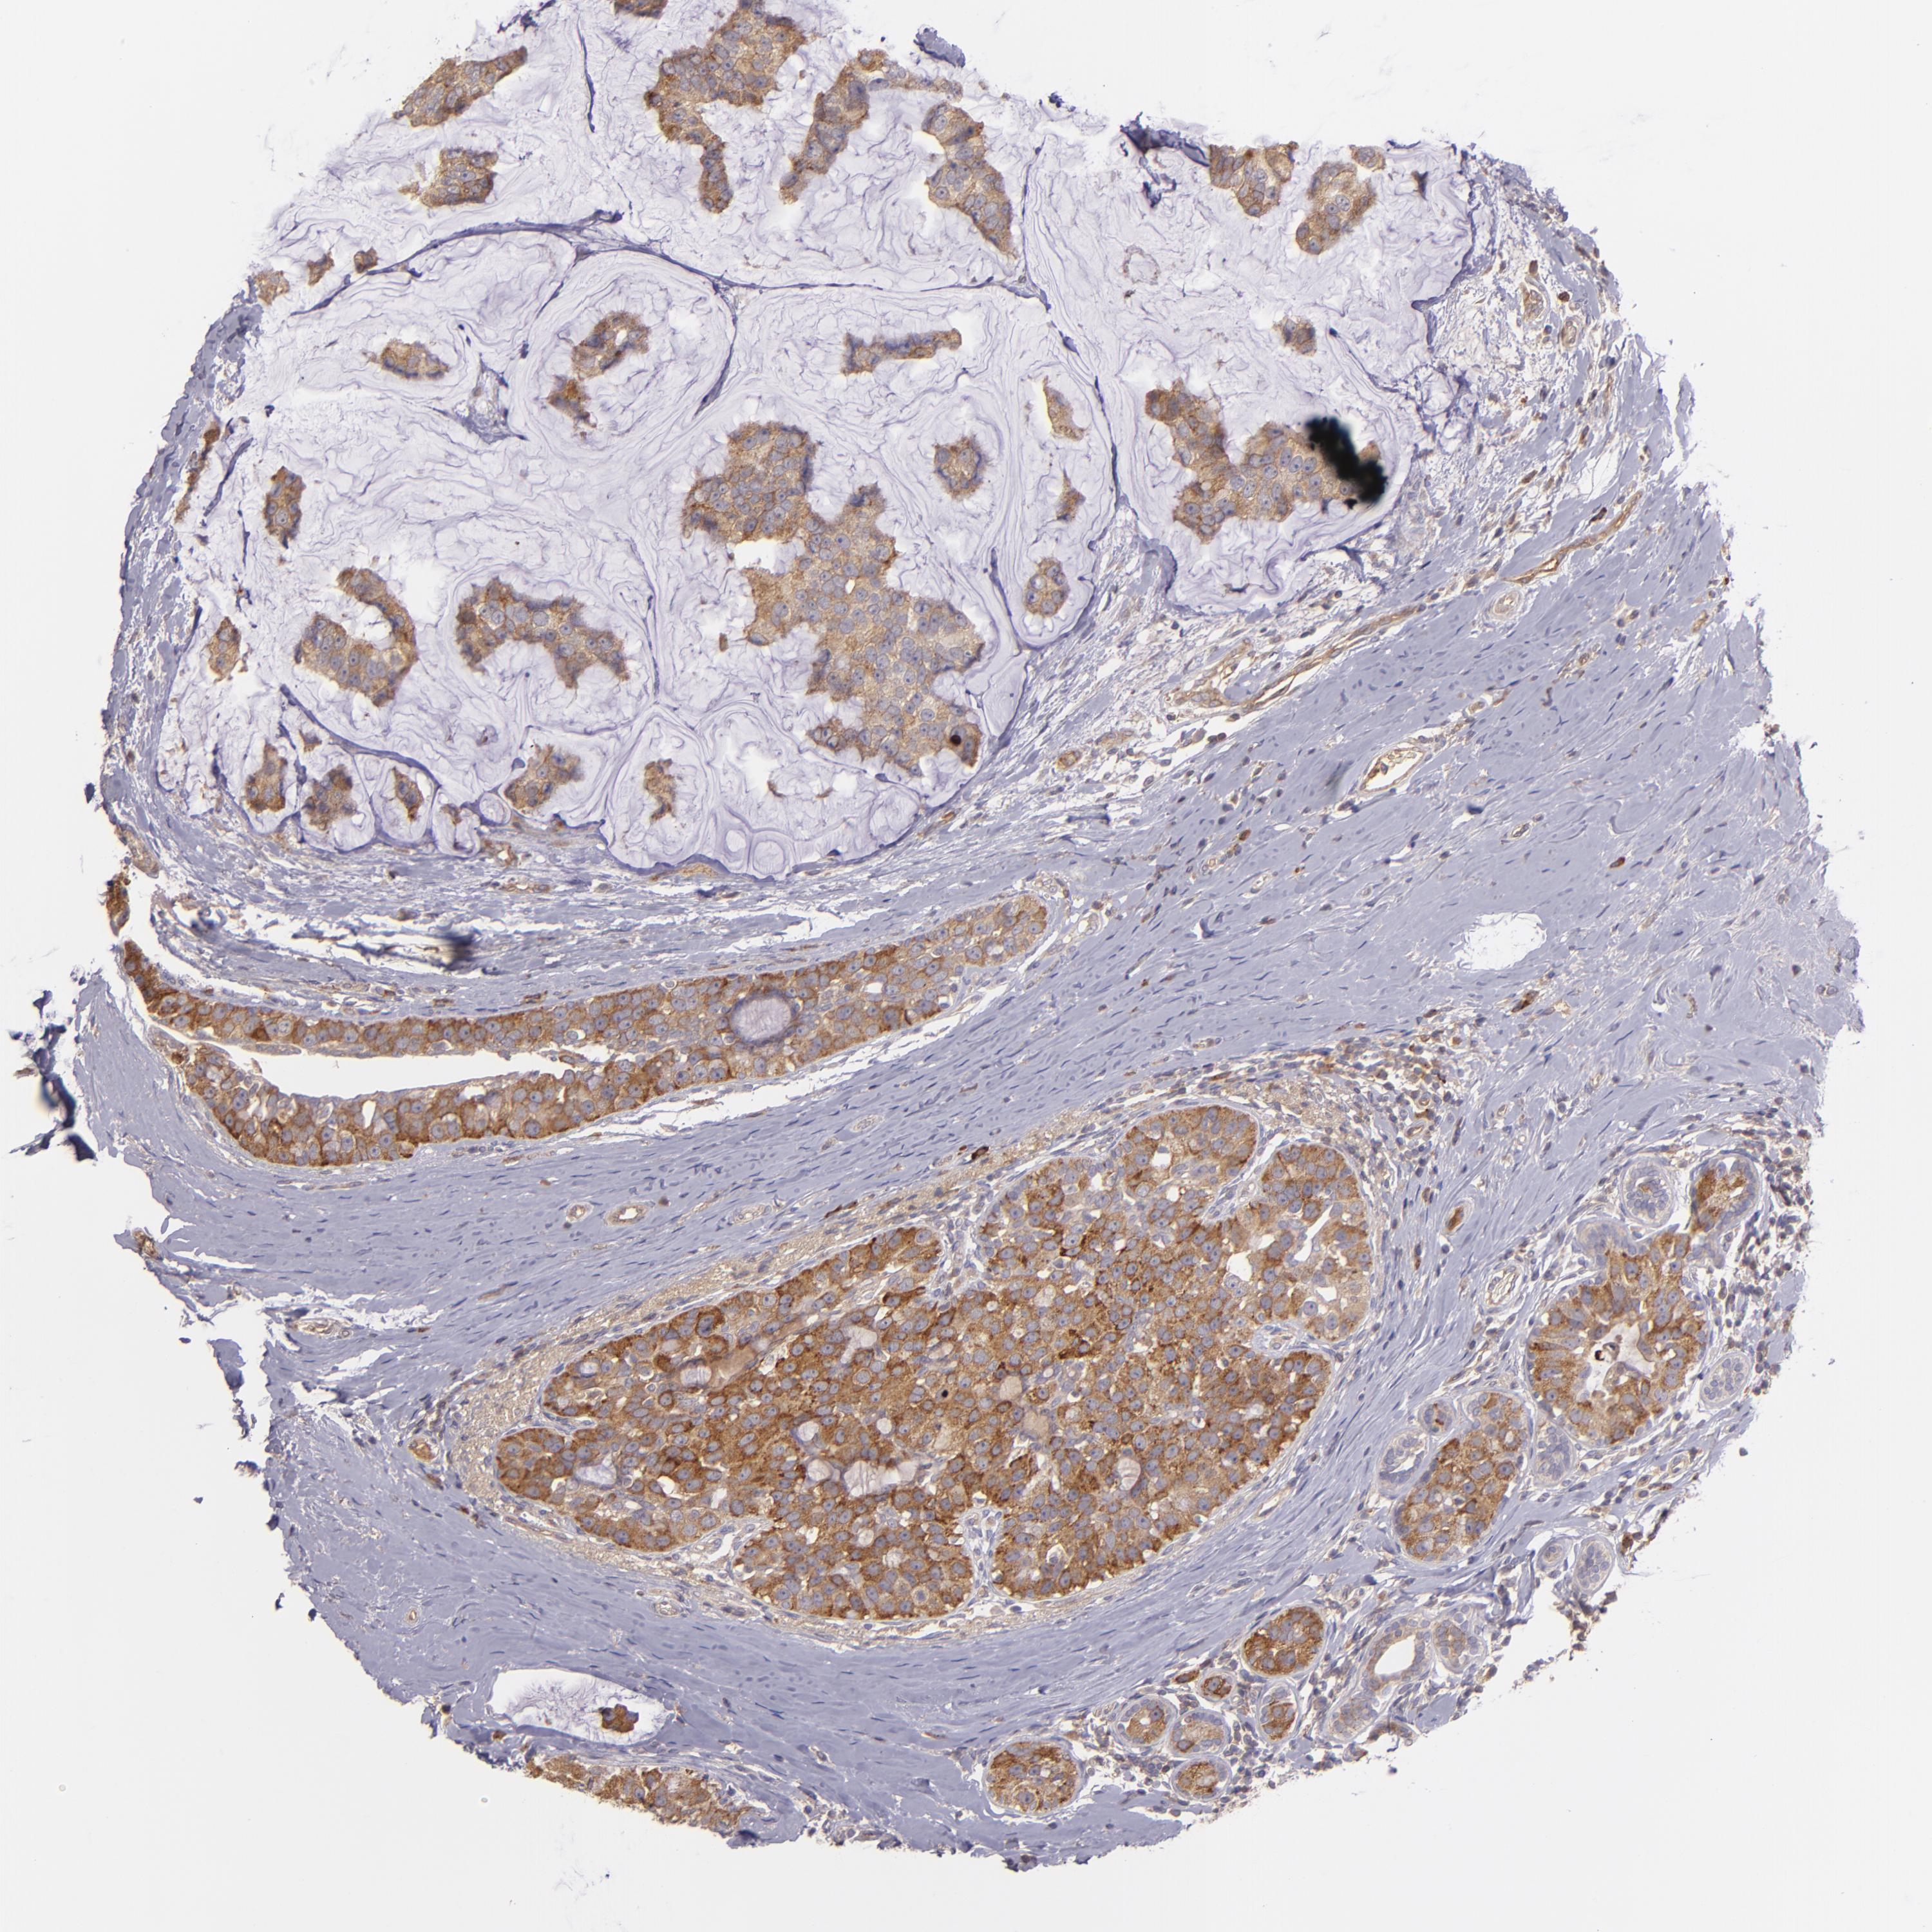

BRCA TCGA BRCA VALIDATION PROTEIN EXPRESSION

ANTIBODIES

AND

VALIDATION